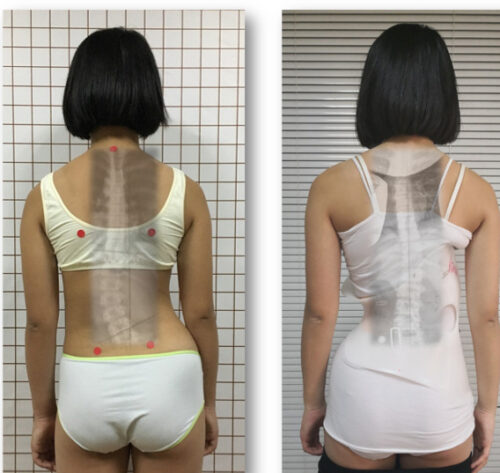

يُعد اعوجاج العمود الفقري مجهول السبب عند المراهقين (Adolescent Idiopathic Scoliosis – AIS) من أكثر اضطرابات العمود الفقري شيوعًا في مرحلة النمو، ويُعتبر العلاج بحزام اعوجاج العمود الفقري (Brace) الطريقة التحفظية الأكثر استخدامًا لتصحيح الانحناء ومنع تفاقمه.

يُستخدم حزام اعوجاج العمود الفقري كخيار علاجي غير جراحي لتقليل درجة الانحناء ومنع تزايده أثناء فترة النمو السريع.

يتم تصميم الحزام بشكل مخصص لكل مريض بناءً على زاوية الاعوجاج (زاوية كوب)، ومكان الانحناء، وسن المريض، ومستوى نمو العظام.

ويُنصح باستخدام الحزام خصوصًا عندما تكون زاوية الانحناء بين 20 و40 درجة، ولم يكتمل بعد النضج العظمي.

وأكد الباحثون أن شكل الحزام وتصميمه ووزنه من أكثر العوامل التي تؤثر في مدى رضا المريض والتزامه بالعلاج.

التصميم المريح والجذاب لحزام اعوجاج العمود الفقري يساعد على زيادة رضا المريض والتزامه بالعلاج.

تخفيف الوزن وتحسين المواد المستخدمة في صناعة الحزام يُقلل من الشعور بعدم الراحة.

التطور الكبير في تصميم الأحزمة الطبية جعل علاج اعوجاج العمود الفقري عند المراهقين أكثر نجاحًا وأقل إزعاجًا. باستخدام تقنيات التصوير الثلاثي الأبعاد والمحاكاة الرقمية، أصبح الحزام أكثر خفة وراحة، ويعطي نتائج أفضل في تصحيح الانحناء والتواء العمود الفقري.